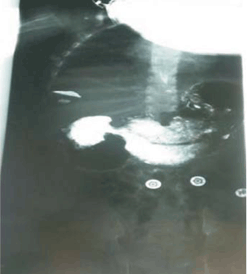

Se reiteran estudios imagenológicos con una nueva ecografía abdominal que muestra dilatación de cámara gástrica marcada y de las dos primeras porciones del duodeno e imagen sugestiva de obstrucción duodenal parcial a nivel de D2. La (Figura 3) muestra la radiografía de abdomen de pie gran dilatación gástrica, con signo de la doble burbuja. La (Figura 4) y la (Figura 5) muestran el estudio contrastado gastroduodenal que constató obstrucción duodenal a nivel de segunda porción con pasaje a sectores distales. Sin evidencias de malrotación u otras anomalías.

Figura 4: Estudio radiológico contrastado gastroduodenal. Se observa obstrucción en D2 con pasaje de contraste distal.

Figura 5: Estudio radiológico contrastado gastroduodenal. Se observa obstrucción en D2 con pasaje de contraste distal.

A los 13 meses de edad ingresa por oclusión intestinal con deshidratación. La radiografía de abdomen de pie mostraba el signo de la “doble burbuja” (estómago y primera porción del duodeno distendidos, con pasaje parcial de aire de manera distal), que confirmaba el diagnóstico de oclusión intestinal alta.